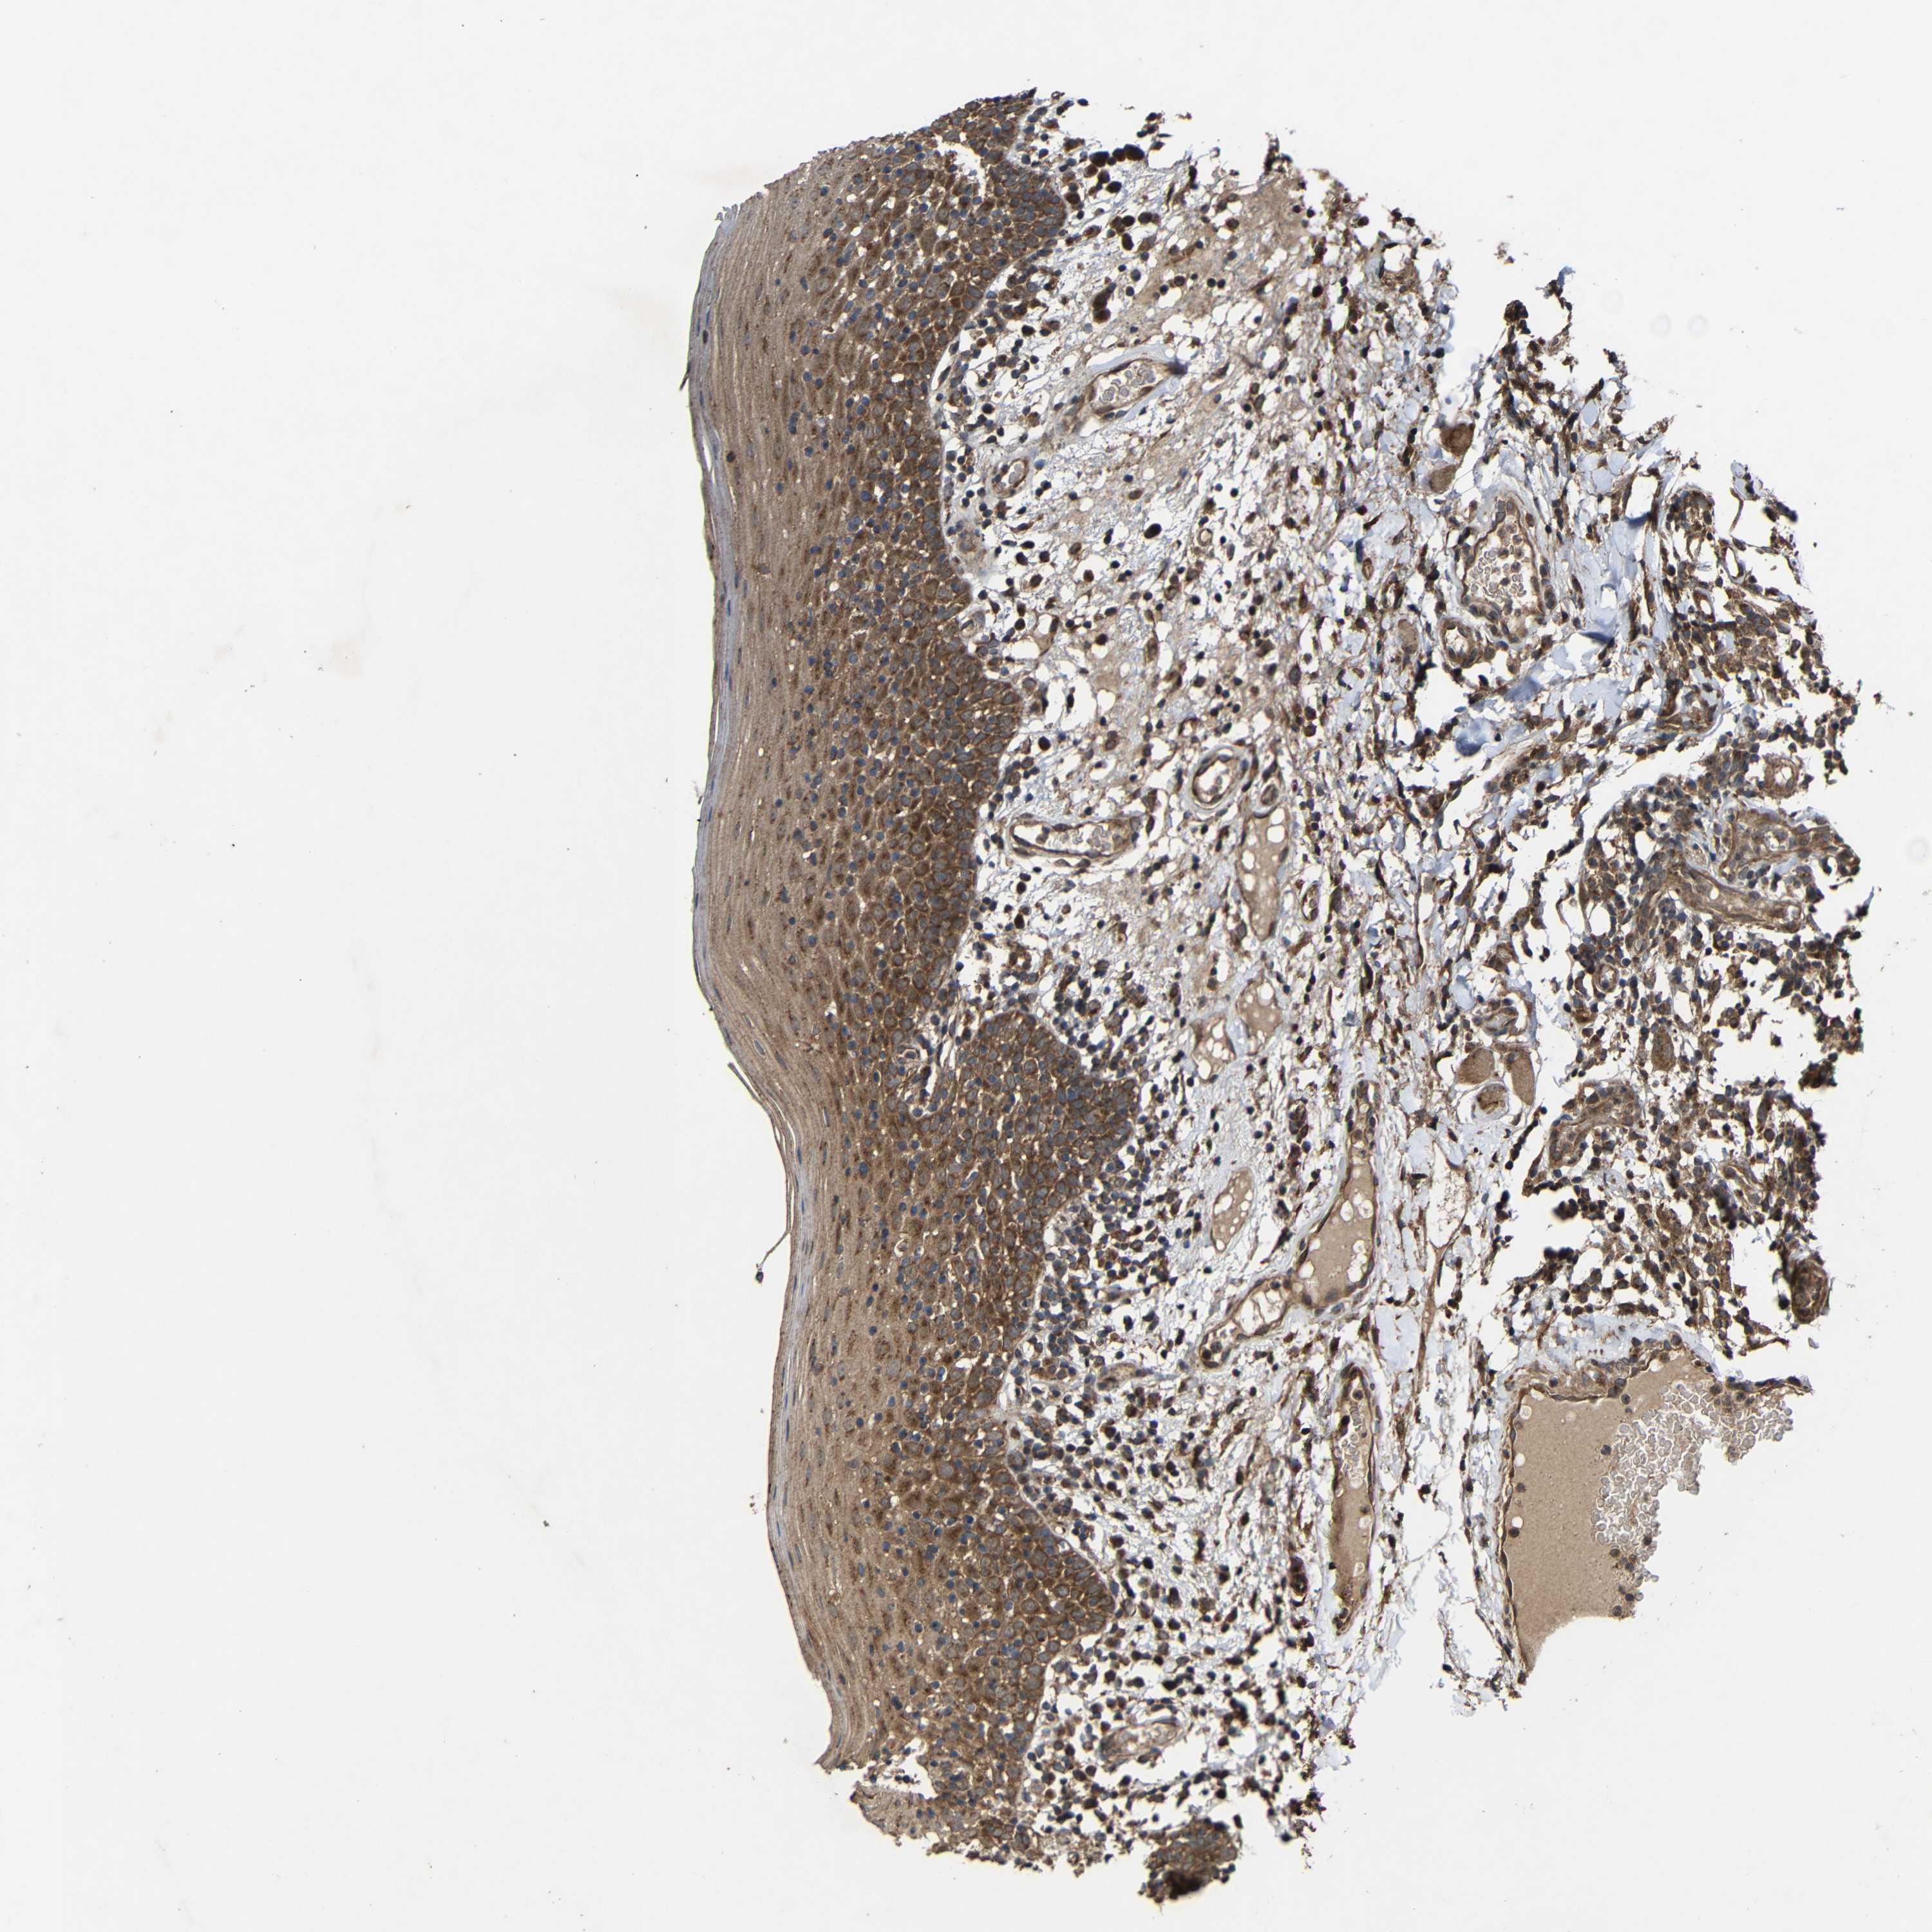

TISSUE PRIMARY DATA ORAL MUCOSA Show tissue menu

ORAL MUCOSA - Antibody stainingi

Antibody staining in the annotated cell types in the current human tissue is reported as not detected, low, medium, or high, based on conventional immunohistochemistry profiling in selected tissues. This score is based on the combination of the staining intensity and fraction of stained cells.

Each image is clickable and will lead to virtual microscopy that enables deeper exploration of all samples and also displays staining intensity scores, fraction scores and subcellular localization as well as patient and tissue information for each sample.

Antibody HPA011294Antibody HPA012819

Squamous epithelial cells HighHigh